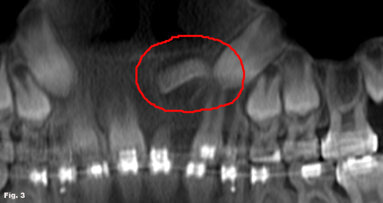

The GXCB-500 HD has a unique, adjustable 3-D medium field of view that can be sized from as large as 8 x 14 cm to as small as 2 x 8 cm. This allows for the greatest flexibility of treatment covering a host of procedures from TMJ to implants to endo.

As an endodontist, I was trained to get to the root of the problem. While this is literally my job and my passion, in the past it has also been a source of ...